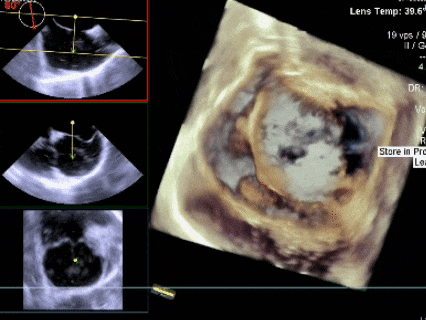

测量膨出瘤基底宽19.61mm,深7.00mm

房间隔总长44.22mm,缺损大小14.80mm

三维下可见房间隔缺损

选伞考量:(分型)继发孔型房间隔缺损合并膨出瘤,房间隔中部局部呈瘤样向右房膨出范围约11×19mm,房间隔中部回声中断约11×9mm。术中复测膨出瘤基底宽19.61mm;房间隔总长44.22mm,缺损大小14.80mm。综合考量选择BDASD-II 24封堵器,配16F鞘管施行介入封堵。